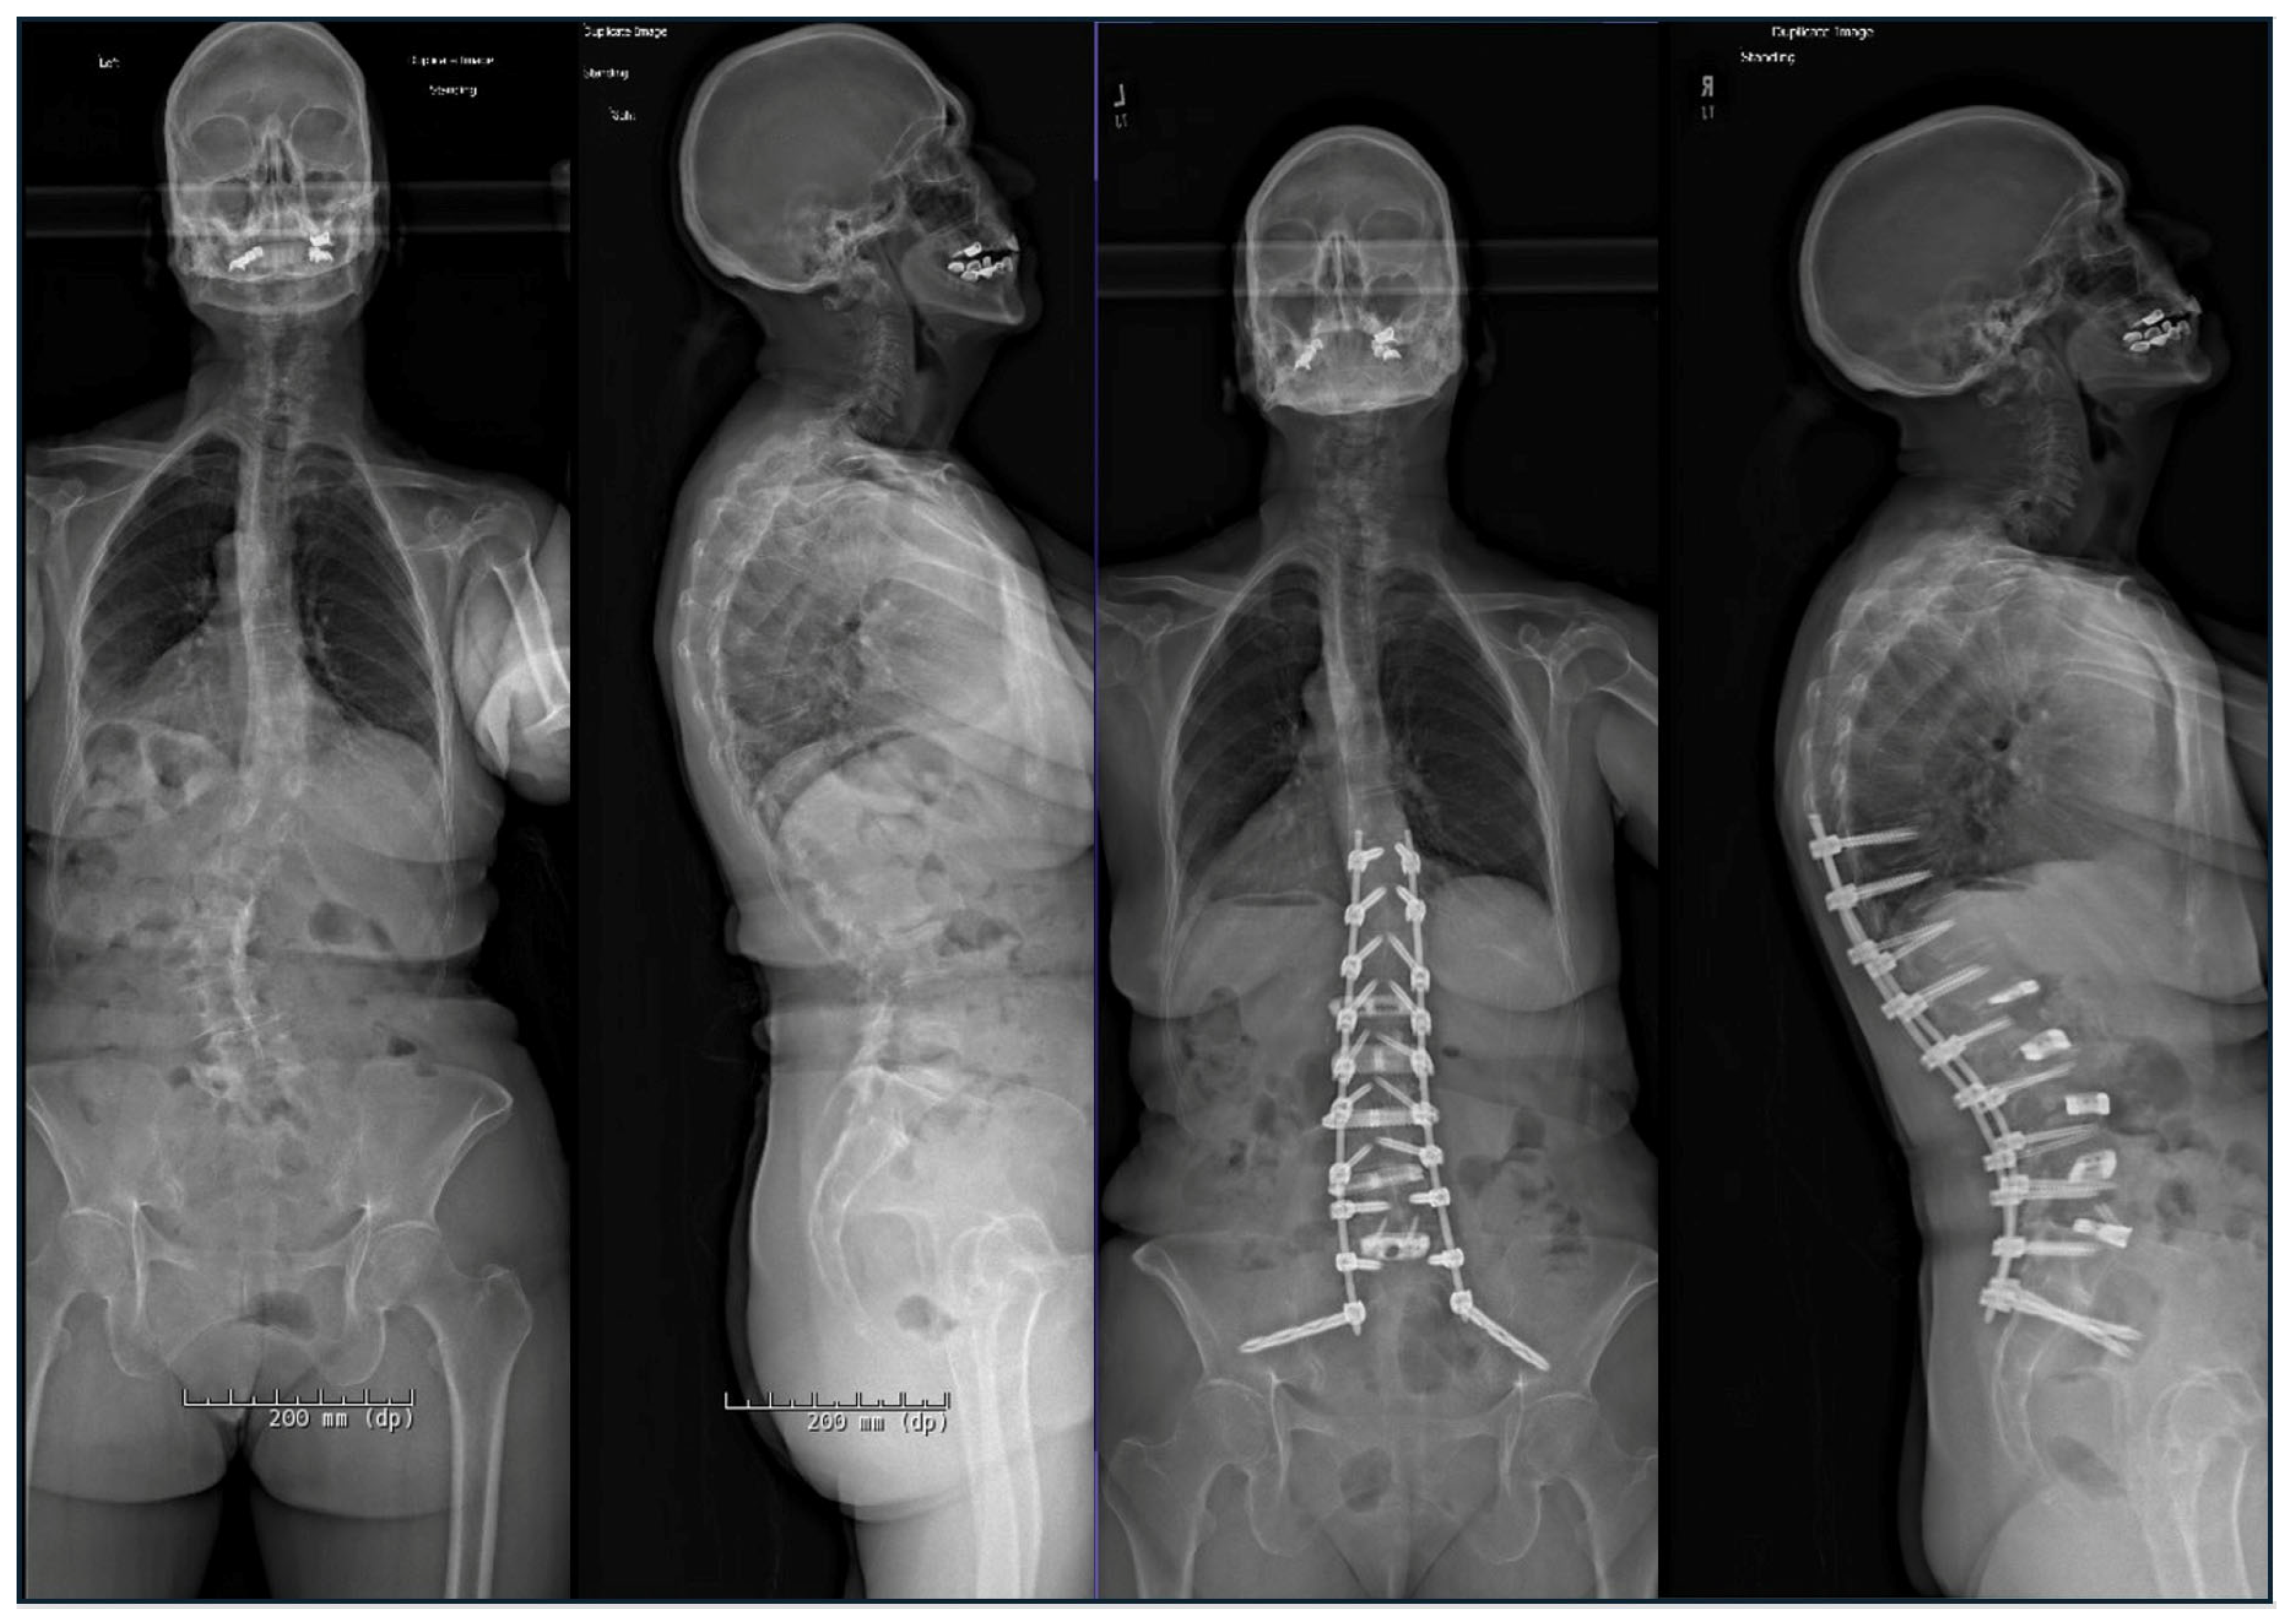

2.1. Advances in Deformity Imaging

2.4. Preoperative Planning and Predictive Modeling

2.7. Custom Patient-Specific Rods